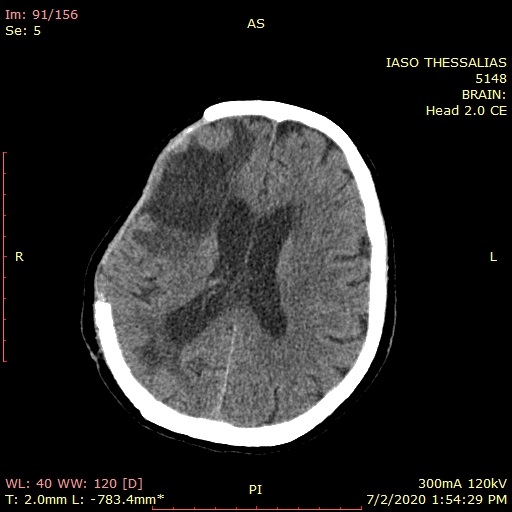

Προ διμήνου αντιμετωπίστηκε επιτυχώς ένα περιστατικό με εκτεταμένη ενδοεγκεφαλική αιμορραγία δεξιού ημισφαιρίου σε ασθενή που προσήλθε στο ΙΑΣΩ Θεσσαλίας με μειωμένο επίπεδο συνείδησης, το οποίο εκτιμήθηκε έγκαιρα από τον εφημερεύοντα Παθολόγο και Διευθυντή της Α΄ Παθολογικής Κλινικής κ. Ευάγγελο Αδαμόπουλο και εν συνεχεία παραπέμφθηκε στον Νευροχειρουργό κ. Ιορδάνη Γεωργιάδη. Η έγκαιρη εκτίμηση είχε ως αποτέλεσμα η ασθενής να υποβληθεί σε επείγουσα αξονική τομογραφία εγκεφάλου και εν συνεχεία να οδηγηθεί στο χειρουργείο προς αποκατάσταση της βλάβης.

1η ΜΕΤΕΓΧΕΙΡΗΤΙΚΗ ΑΞΟΝΙΚΗ ΜΕΤΑ ΤΟ 1ο ΧΕΙΡΟΥΡΓΕΙΟ[/bt_column] [bt_column class="bt-column col-xs-12 col-sm-12 col-md-6 col-lg-6 center"]

1η ΜΕΤΕΓΧΕΙΡΗΤΙΚΗ ΑΞΟΝΙΚΗ ΜΕΤΑ ΤΟ 2ο ΧΕΙΡΟΥΡΓΕΙΟ[/bt_column] [/bt_columns]

2η ΜΕΤΕΓΧΕΙΡΗΤΙΚΗ ΑΞΟΝΙΚΗ ΕΝΑ ΜΗΝΑ ΜΕΤΑ ΤΟ 1ο ΧΕΙΡΟΥΡΓΕΙΟ[/bt_column] [bt_column class="bt-column col-xs-12 col-sm-12 col-md-6 col-lg-6 center"]

3η ΜΕΤΕΓΧΕΙΡΗΤΙΚΗ ΑΞΟΝΙΚΗ ΔΥΟ ΜΗΝΕΣ ΜΕΤΑ ΤΟ 1ο ΧΕΙΡΟΥΡΓΕΙΟ[/bt_column] [/bt_columns]